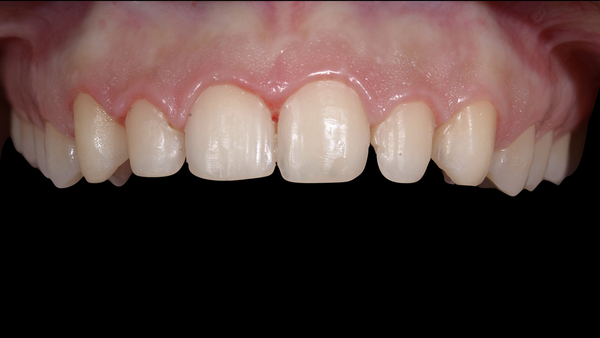

Fig. 1. Fotografia iniziale della paziente.